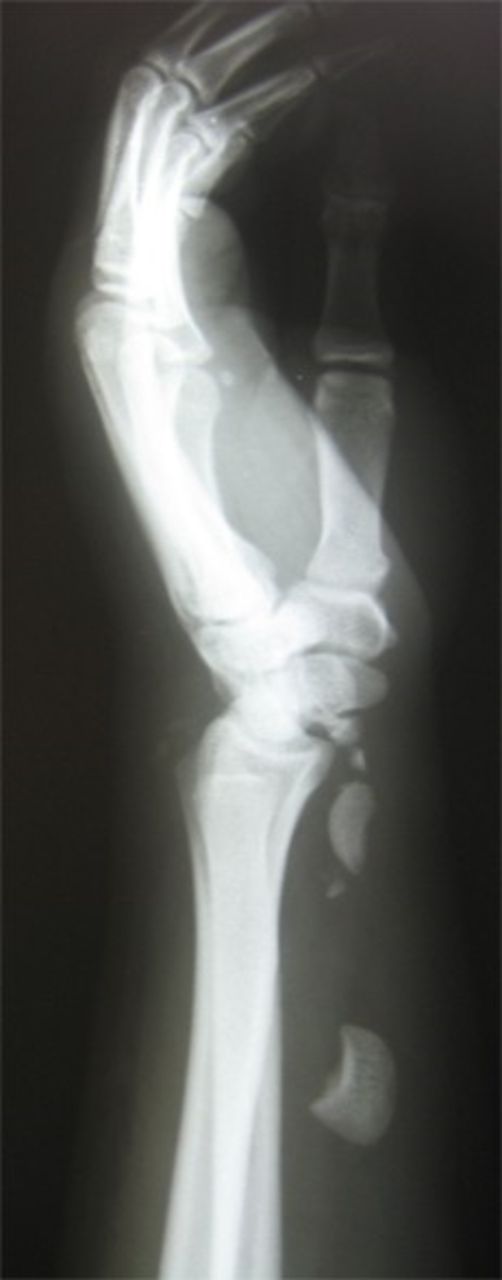

Pins were removed six weeks later, and the cast was discarded ten weeks later. Active and passive range of wrist motion and muscle strengthening exercises were begun. The patient didn’t refer for follow-ups. After two years, he came back with pain, limited motion, and weakness in grip and grasp. Radiographs showed osteonecrosis of lunate and proximal scaphoid. Also, static scapholunate dissociation with signs of mild arthritis was obvious (Figure 2a & 2b).

Posteroanterior and lateral radiographs of left wrist two years after operation show increased density of lunate and proximal scaphoid with subtle arthritic changes. Scapholunate dissociation (Terry-Thomas sign) and dorsal intercalated segment instability are seen.